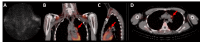

The classic clinical vignette of primary hyperparathyroidism is well described as "bones, stones, abdominal moans, and psychiatric overtones" to reflect the effects of excess parathyroid hormone (PTH) and calcium. Most commonly, primary hyperparathyroidism is due to a functional parathyroid adenoma situated by the thyroid gland. Rarely, the primary focus of autonomously produced PTH is located ectopically within the mediastinum. A 19-year-old Caucasian female with no relevant past medical history presented to the emergency department with tachycardia, nausea, vomiting, and a five-day history of vague, mid-abdominal pain. Initial computed tomography (CT) with contrast of the abdomen and pelvis was negative for acute findings, and she subsequently underwent biochemical screening. The patient was found to have elevated serum calcium and PTH, raising suspicion for the diagnosis of primary hyperparathyroidism. Further evaluation for a parathyroid adenoma was negative by a CT scan of the neck and thyroid ultrasound. A nuclear medicine parathyroid single-photon emission computed tomography (SPECT)/CT with technetium (Tc) 99m sestamibi found an abnormal nodular uptake within the left prevascular mediastinum suggestive of an ectopic parathyroid adenoma. A left-sided, video-assisted thoracoscopic surgery (VATS) with successful excision of the ectopic mediastinal parathyroid adenoma was performed. Surgical pathology revealed that the parathyroid adenoma was completely excised and surrounded by thymus and adipose tissue. The patient tolerated the procedure well and was discharged without further complications. The rarity of mediastinal, intrathymic parathyroid adenomas resulted in delayed diagnosis in this patient, understandably so as errant embryogenesis does not occur commonly. Visualization with SPECT/CT and successful specimen excision by minimally invasive VATS resulted in the accurate diagnosis and ultimate cure of this patient's primary hyperparathyroidism.